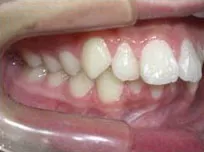

症例1

| 治療期間 | 11ヶ月(2021年6月〜2022年5月) |

| 費用 | 495,000円(税込) |

| リスクや副作用 | 成長期が終わった18歳以降に、2期矯正が必要になることがある |